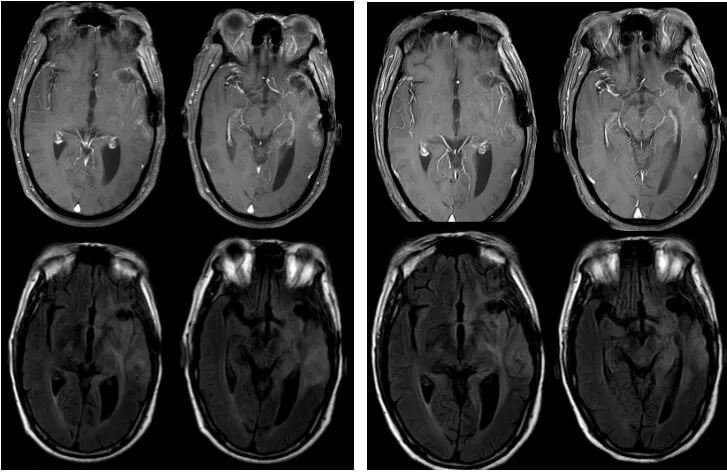

图5. 替尼泊苷联合贝伐珠单抗治疗后,病灶得到有效控制

令人振奋的是,仅仅经过两个周期的治疗,2023年9月的复查MRI便显示,肿瘤强化范围较前略有缩小,疗效评估为疾病稳定(SD)。这意味着新方案有效遏制了肿瘤的生长。截至2023年12月,经过5个周期的治疗,患者病情持续稳定。